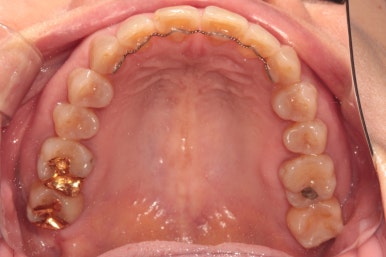

그리고 교합면 사진을 통해 전체적인 진행 상태도 파악할 수 있죠.

교정 시작하고 6개월만에 치아배열이 다되어갑니다.

이제 정말 많이 배열이 완성되었습니다. 아래 앞니를 배열시키느라 시간이 조금 더 걸렸던 것 같아요.

씹는면에서 보아도 상당히 가지런히 완성된 것을 보실 수 있습니다.

교정치료가 끝나면 혀쪽에 유지장치를 붙여드리는데요, 치석이 보다 덜 생기도록 하기 위해서 치아 표면 그대로의 모양을 따라가는 와이어를 제작하여 부착해드리고 있습니다.

조금 더 비용을 들이더라도 정성담긴 모양의 유지장치입니다!!

치아 사이 공간까지도 완벽하게 밀착하고 지나가야 좋은 고정식 유지장치입니다. 그래야 치석도 덜 생기고 관리가 편해지시거든요..